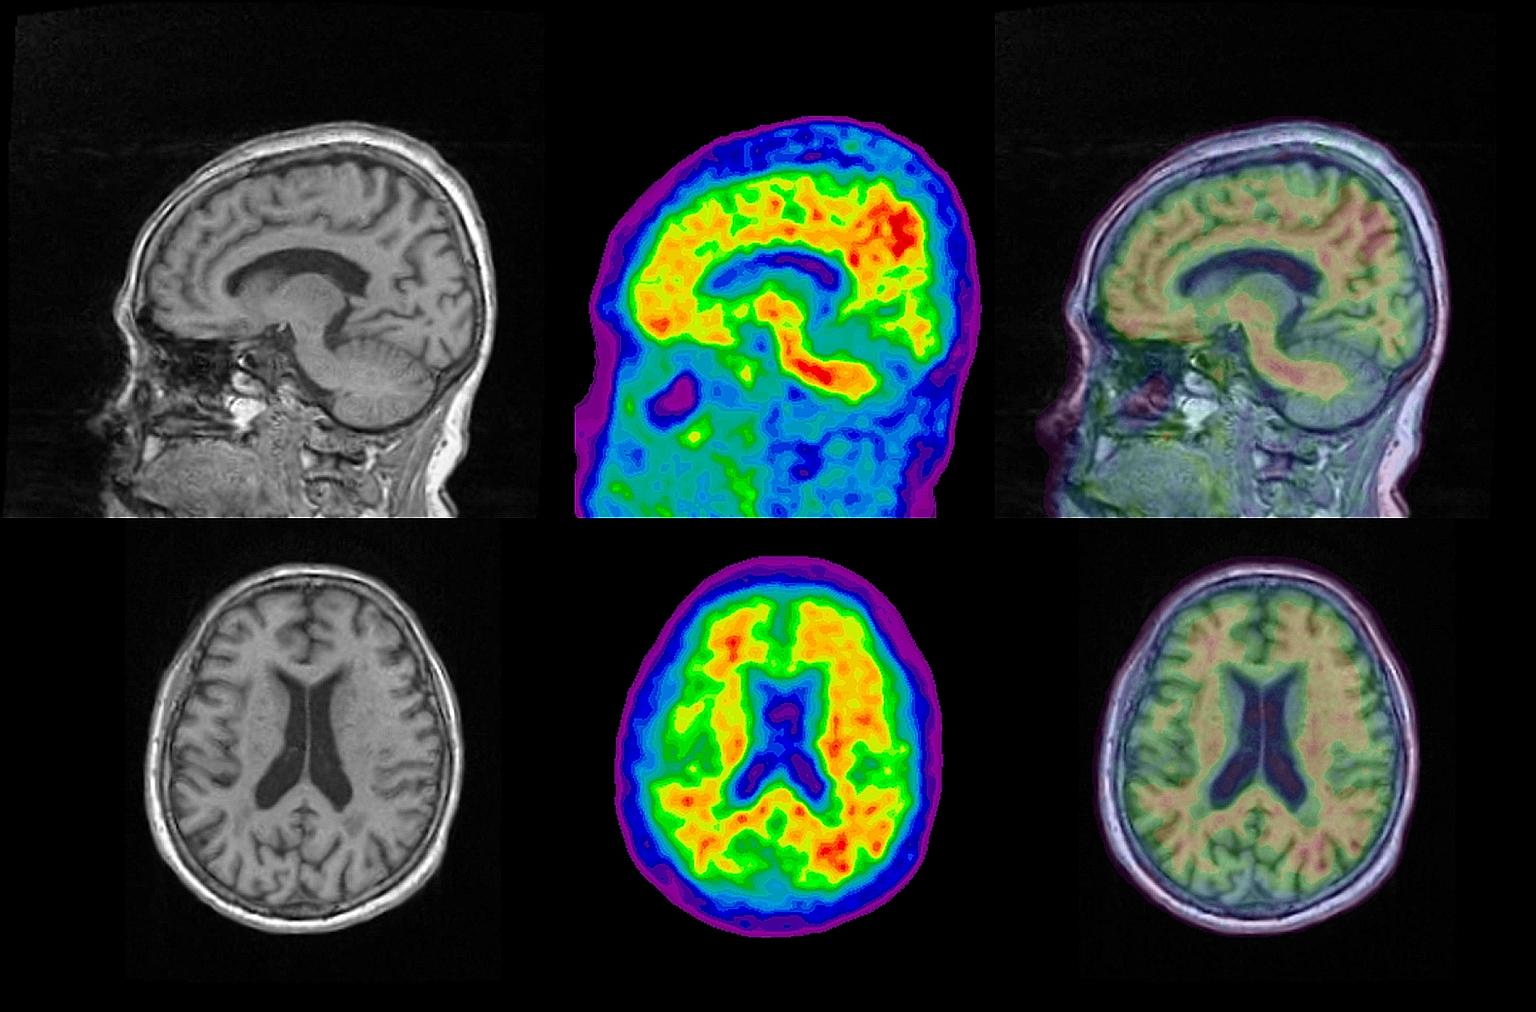

An MRI scan (left) shows brain structure, while a PET scan (centre) lets researchers see amyloid presence in red. Combining the two images (right) could help doctors find out which parts of the brain have a build-up of the protein linked to Alzheimer's disease, paving the way for better treatment.

PHOTO: CLINICAL IMAGING RESEARCH CENTRE